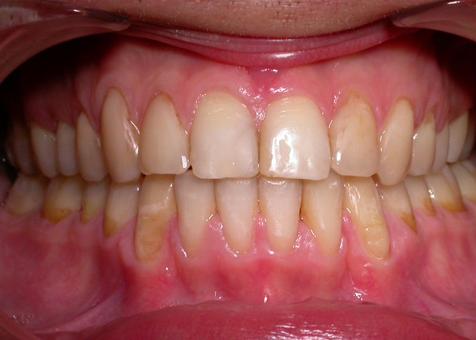

Лечение проводилось с апроксимальной сепарацией эмали зубов. Применялись керамические брекеты.

Результат получен спустя 18 месяцев после начала лечения